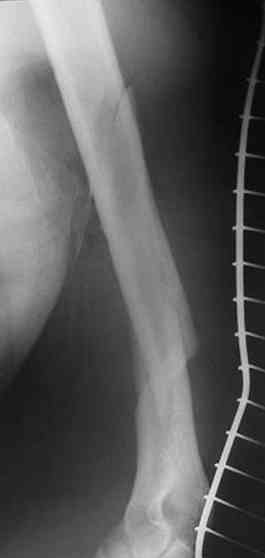

Уважаемые коллег, могу поделиться личным опытом лечения огнестрельных переломов в Республике Йемен. 230-250 больных за год. Пользуюсь класс, Густилло-Андерсон

Подход при 1,11, некоторых 111 А переломах "нетрадиционный -сберегательная хирургическая обработка, СОХРАНЕНИЕ всех костных отломков, первичный малоинвазивный остеосинтез LCP ( не нарушается периостальное и эндостальное кровоснабжение отломков, а при штифтовании нарушается эндост. кровоснабжение и риск медулярного остеомиелита), проточное дренирование, первичное закрытие ран, БЕЗ НАТЯЖЕНИЯ тканей или перв. отсроченные швы. При переломах 111В на первом этапе также СБЕРЕГАТЕЛЬНАЯ обработка с сохранением отломков и АВФ. Через две недели -МАЛОИНВАЗИВНЫЙ остеосинтез LCP

Я делал презентации на многих конференциях в России и за границей, также можно см журнал "ТРАВМ. ОРТОПЕДИЯ РОССИИ №2 2007 и 2 -2008

Привожу один из примеров

Р.S. Привожу клинический пример больного с огн. переломом бедра Густилло- Андерсон 111 А